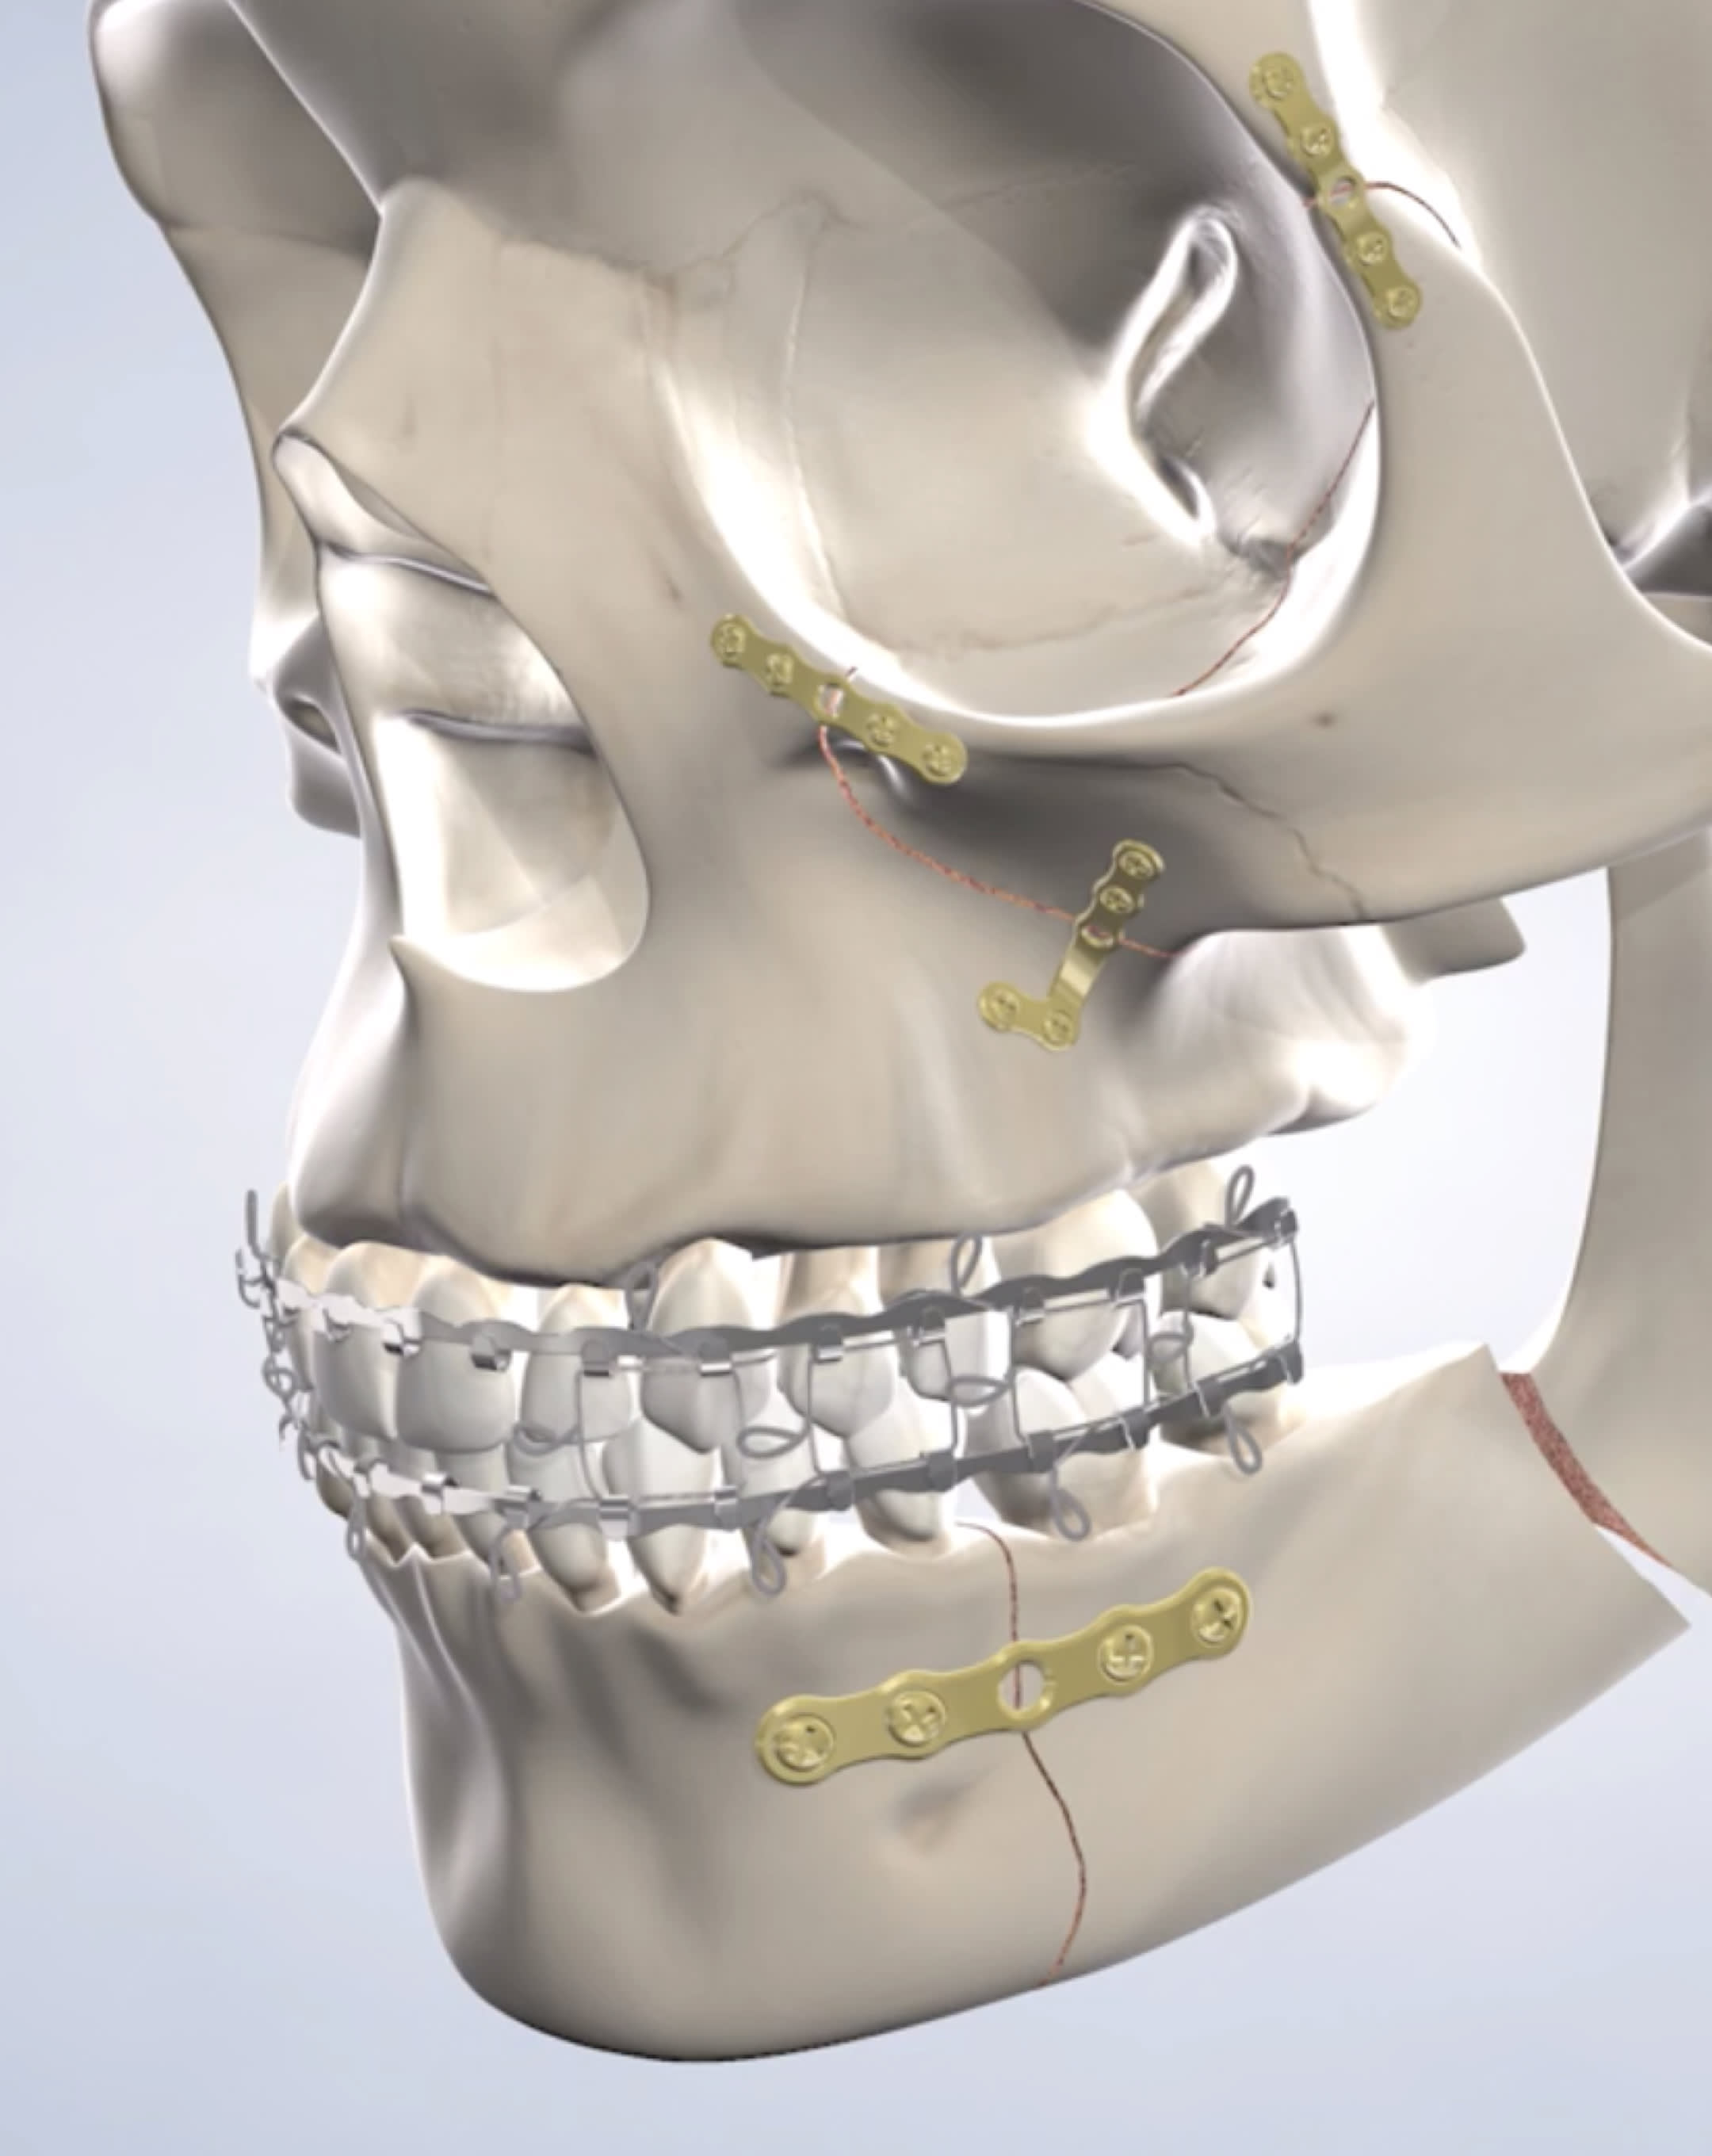

Soft tissue injuries may be treated with sutures, which are placed from within the mouth whenever possible or in less noticeable areas to reduce visible scarring. Bone injuries often require surgery, where your surgeon will use plates or screws to reposition and stabilize the face or jaw bones. Using screws and plates often eliminates the need to wire the jaws shut while they heal.